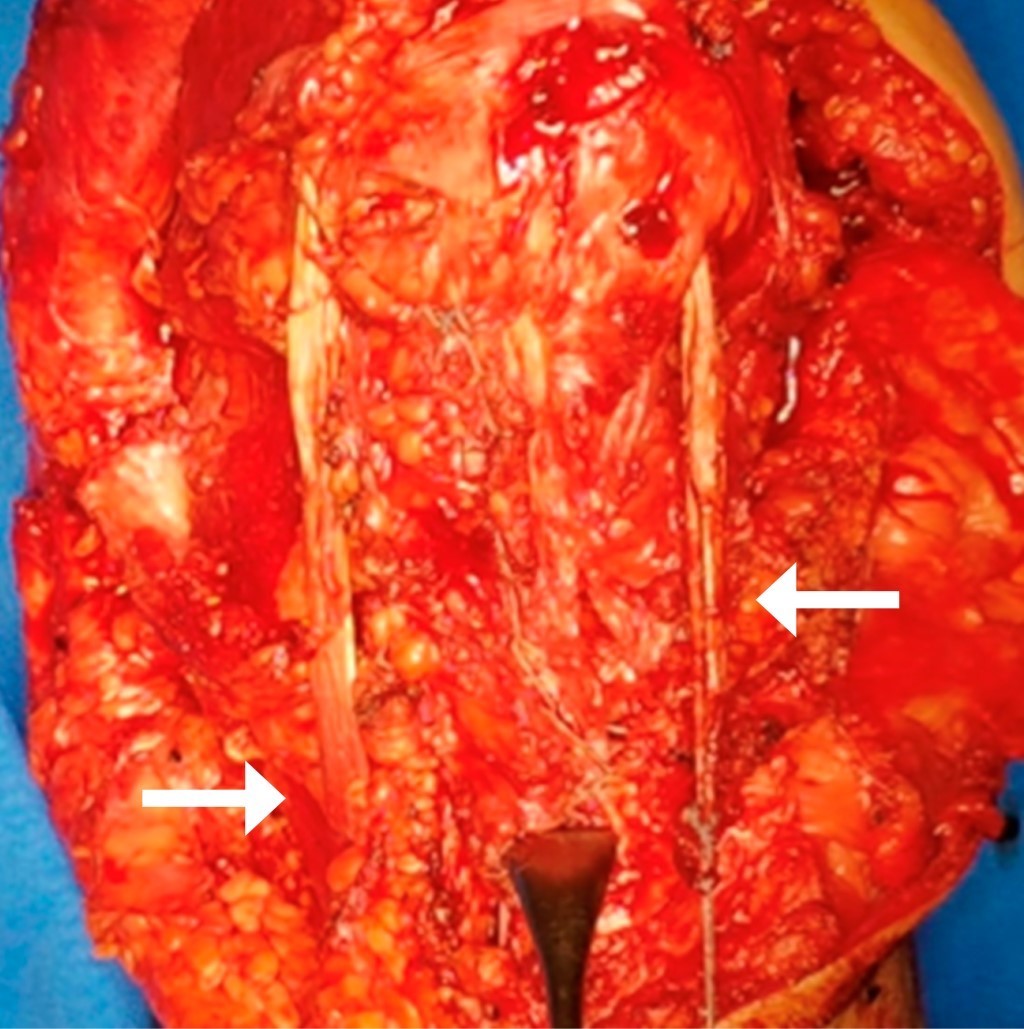

La primera intervención quirúrgica fue reconstruir el tendón rotuliano. Se realizó túnel en rótula de medial a lateral de 4 mm de diámetro en su tercio medio para poder pasar los dos tendones con aguja viuda recta y así poder llevarlos ligeramente medial a tubérculo de Gerdy, previa liberación de toda la musculatura de cuádriceps desde anterior, posterior, medial y lateral. Se trató de descender lo más posible la rótula, con completa extensión de la rodilla. Una vez con la rótula en su mayor descenso, se usaron dos anclas de 5.0 mm para su fijación (Figura 3). Se colocó vendaje de Jones por 15 días con férula glúteo-podálica posterior, con curación en seco de la herida quirúrgica cada semana y valoración.

Figura 3